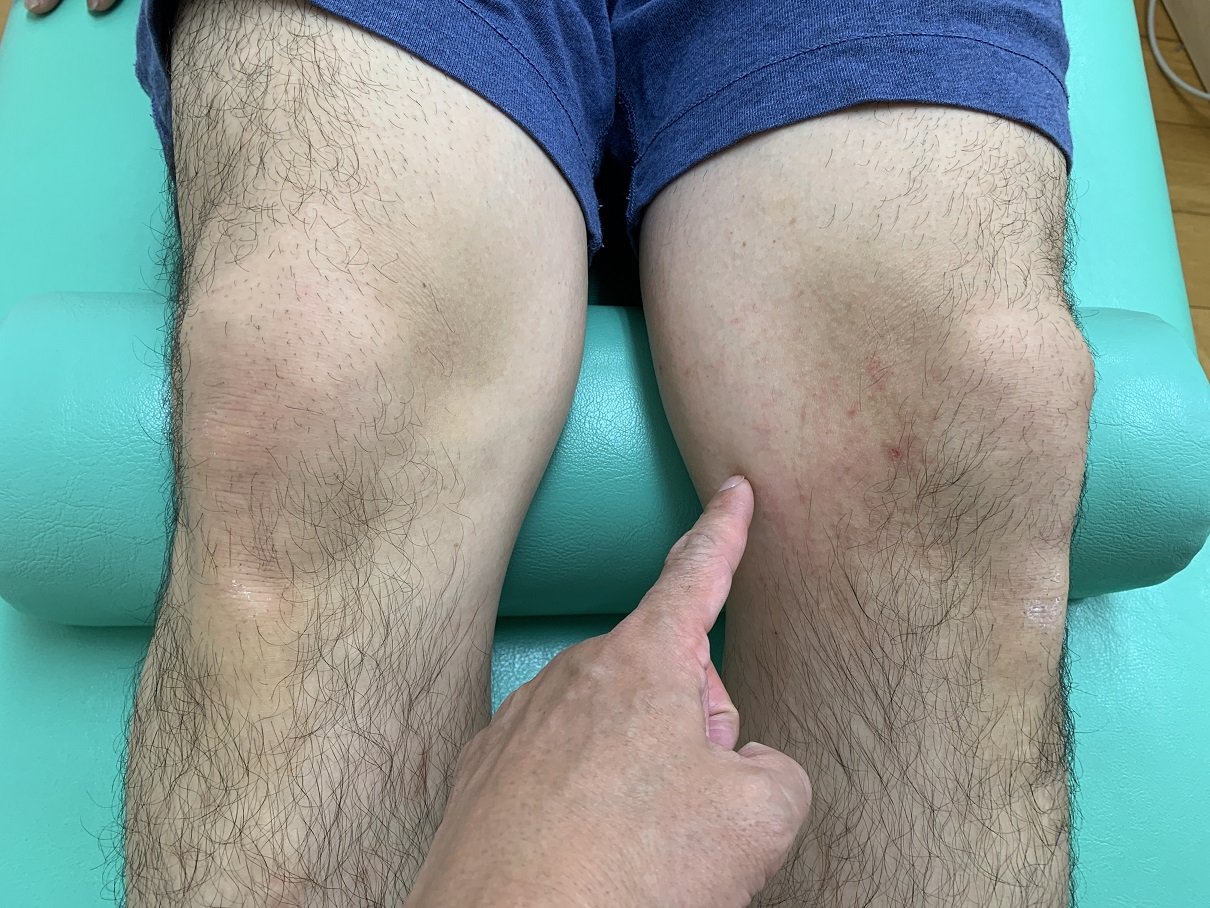

ゴルフ場で歩行中、凹凸部で足をとられた際、転倒した時に、左膝を捻ったと御来院。

いつものように問診、触診、ストレステスト後、エコー検査。